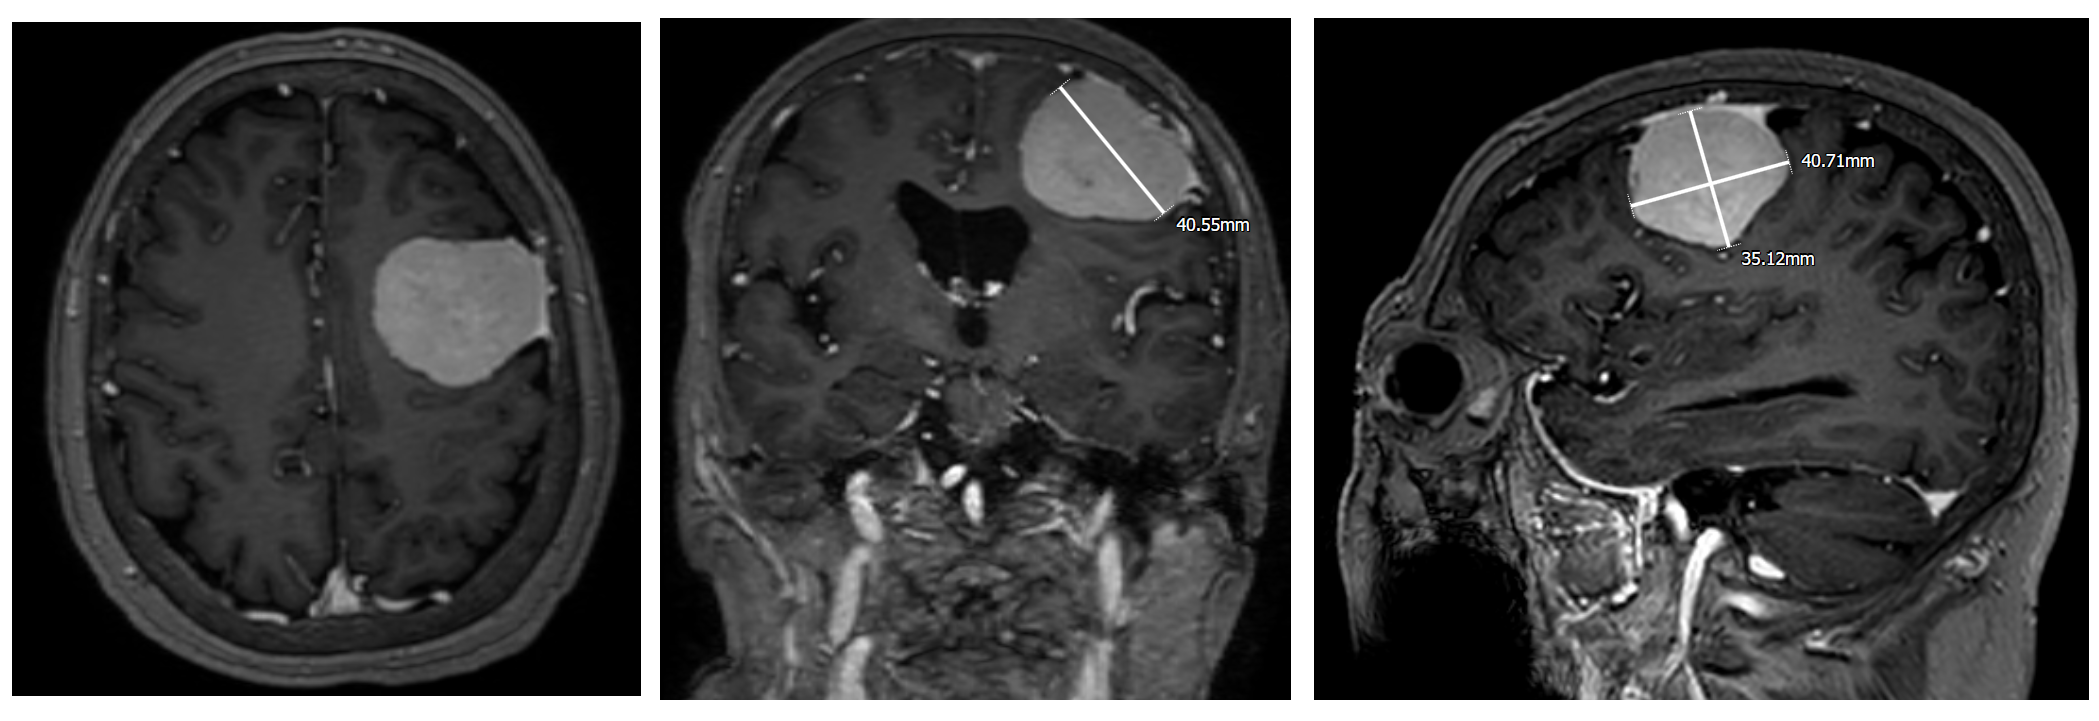

近日笔者完成一例左侧大脑凸面脑膜瘤,最大径4cm,肿瘤虽大,但只是推挤,蛛网膜界面完整,没有脑水肿。

术前MRI